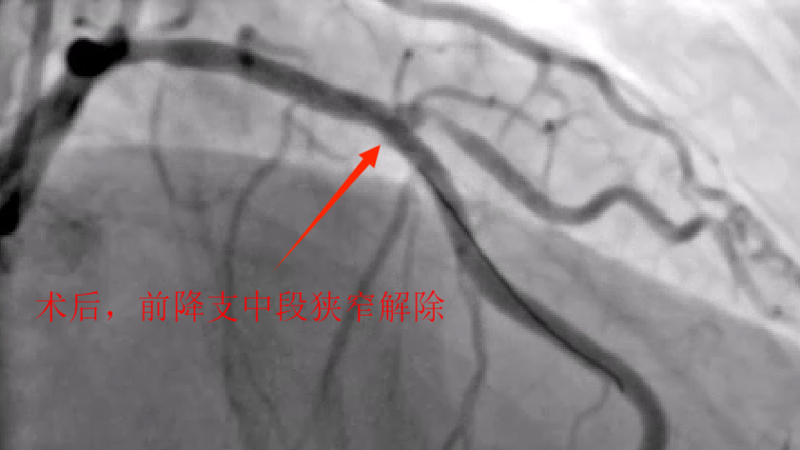

据了解,吴某,男性,58岁,因胸痛就诊,确诊为急性非ST段抬高型心肌梗塞,10多天前有过消化道出血情况,既往有心肌梗塞、痛风、慢性肾功能不全等病史,1年前胃镜提示有胃溃疡病史,口服有多种药物,考虑患者病情危重及复杂,心血管内科介入团队经过讨论后先行冠脉造影后再决定下一步诊疗策略,造影可见:前降支中段发出对角支后极重度狭窄,可见侧支循环右冠中远端,回旋支发出钝缘支后闭塞,可见钝缘支侧支循环回旋支远端;右冠中段闭塞。

经过医护人员精心照顾及治疗,患者各方面情况相对稳定,11月5日心血管内科介入团队再次为患者行冠脉介入治疗。并顺利开通右冠闭塞血管并植入支架恢复正常血流,同期解决前降支极重度狭窄病变并植入支架解除危机。手术总用时1小时40分钟,造影剂用量120ml。